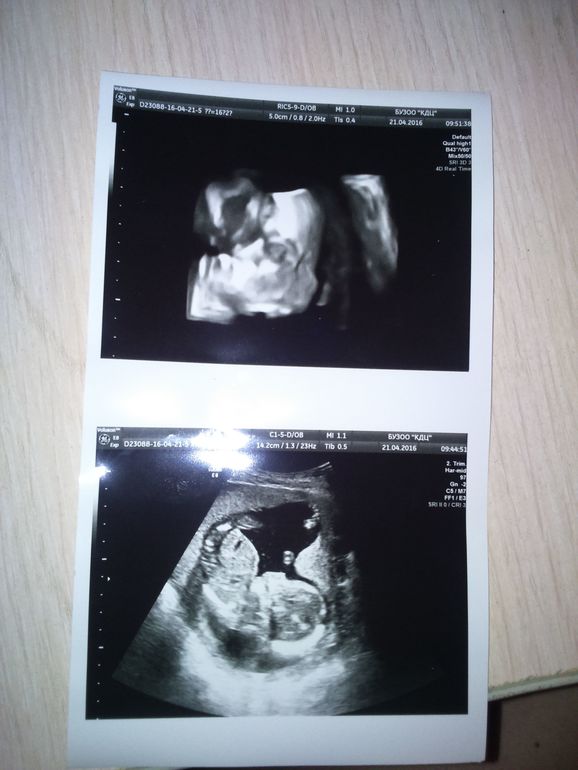

УЗИ!

Результаты: УЗИ, КТГ, доплера, скринингаВчера сходили на узи, и нам сказали, что у нас мальчик!) мое чутье меня обмануло) Наш сынишка👼

Несколько дней чувствую, как что-то бурлит в животе и не могу понять, что это - кишечник или малыш? Для малыша вроде как рано, но раньше такого не было.. Моя мама говорит, что пузыри пускает и на фото даже видно😊